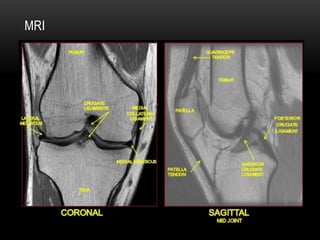

MRI